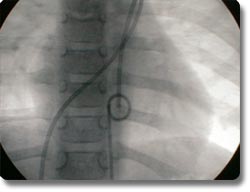

动脉导管未闭、房间隔缺损为先天性心脏发育缺陷,分别形成主动脉、肺动脉间及左右心房间的异常通道,传统治疗方式为外科开胸手术治疗。我科与国外同步开展了非手术经皮动脉导管封堵术及房间隔封堵术,用介入治疗方式矫正异常通道,手术时间30分钟左右,术后2天病员即可康复出院,疗效与外科开胸手术相同。 |